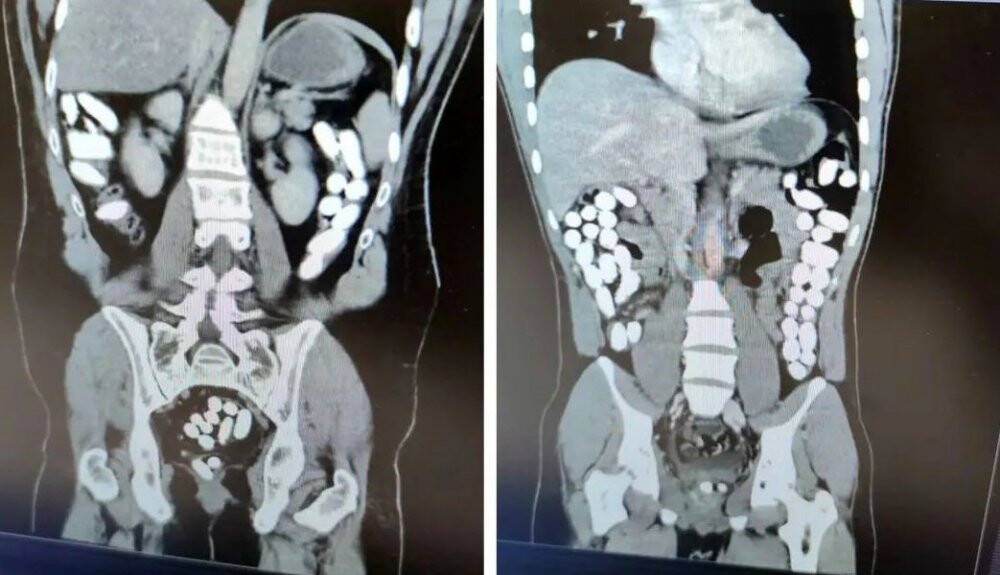

İl Emniyet Müdürlüğü Narkotik Suçlarla Mücadele Şube Müdürlüğü ile Kaçakçılık ve Organize Suçlarla Mücadele Şube Müdürlüğü ekiplerince yapılan çalışmada; Uygulama noktasında durdurulan yolcu otobüsünde yolcu olarak bulunan İran uyruklu A.G. (25) ve E.P. (21) İsimli şahıslara alınan karara istinaden yapılan tomografi çekiminde mide ve bağırsak kısmında uyuşturucu olabileceğini değerlendirilen çokça yabancı cismin olduğu görüldü. Yapılan tetkikler neticesinde A.G. (25) isimli şahıstan 100 parça halinde 847,64 gr gelen Afyon Sakızı, E.P. (21) isimli şahıstan 142 parça halinde 1071,80 gr gelen Afyon Sakızı ele geçirildi.